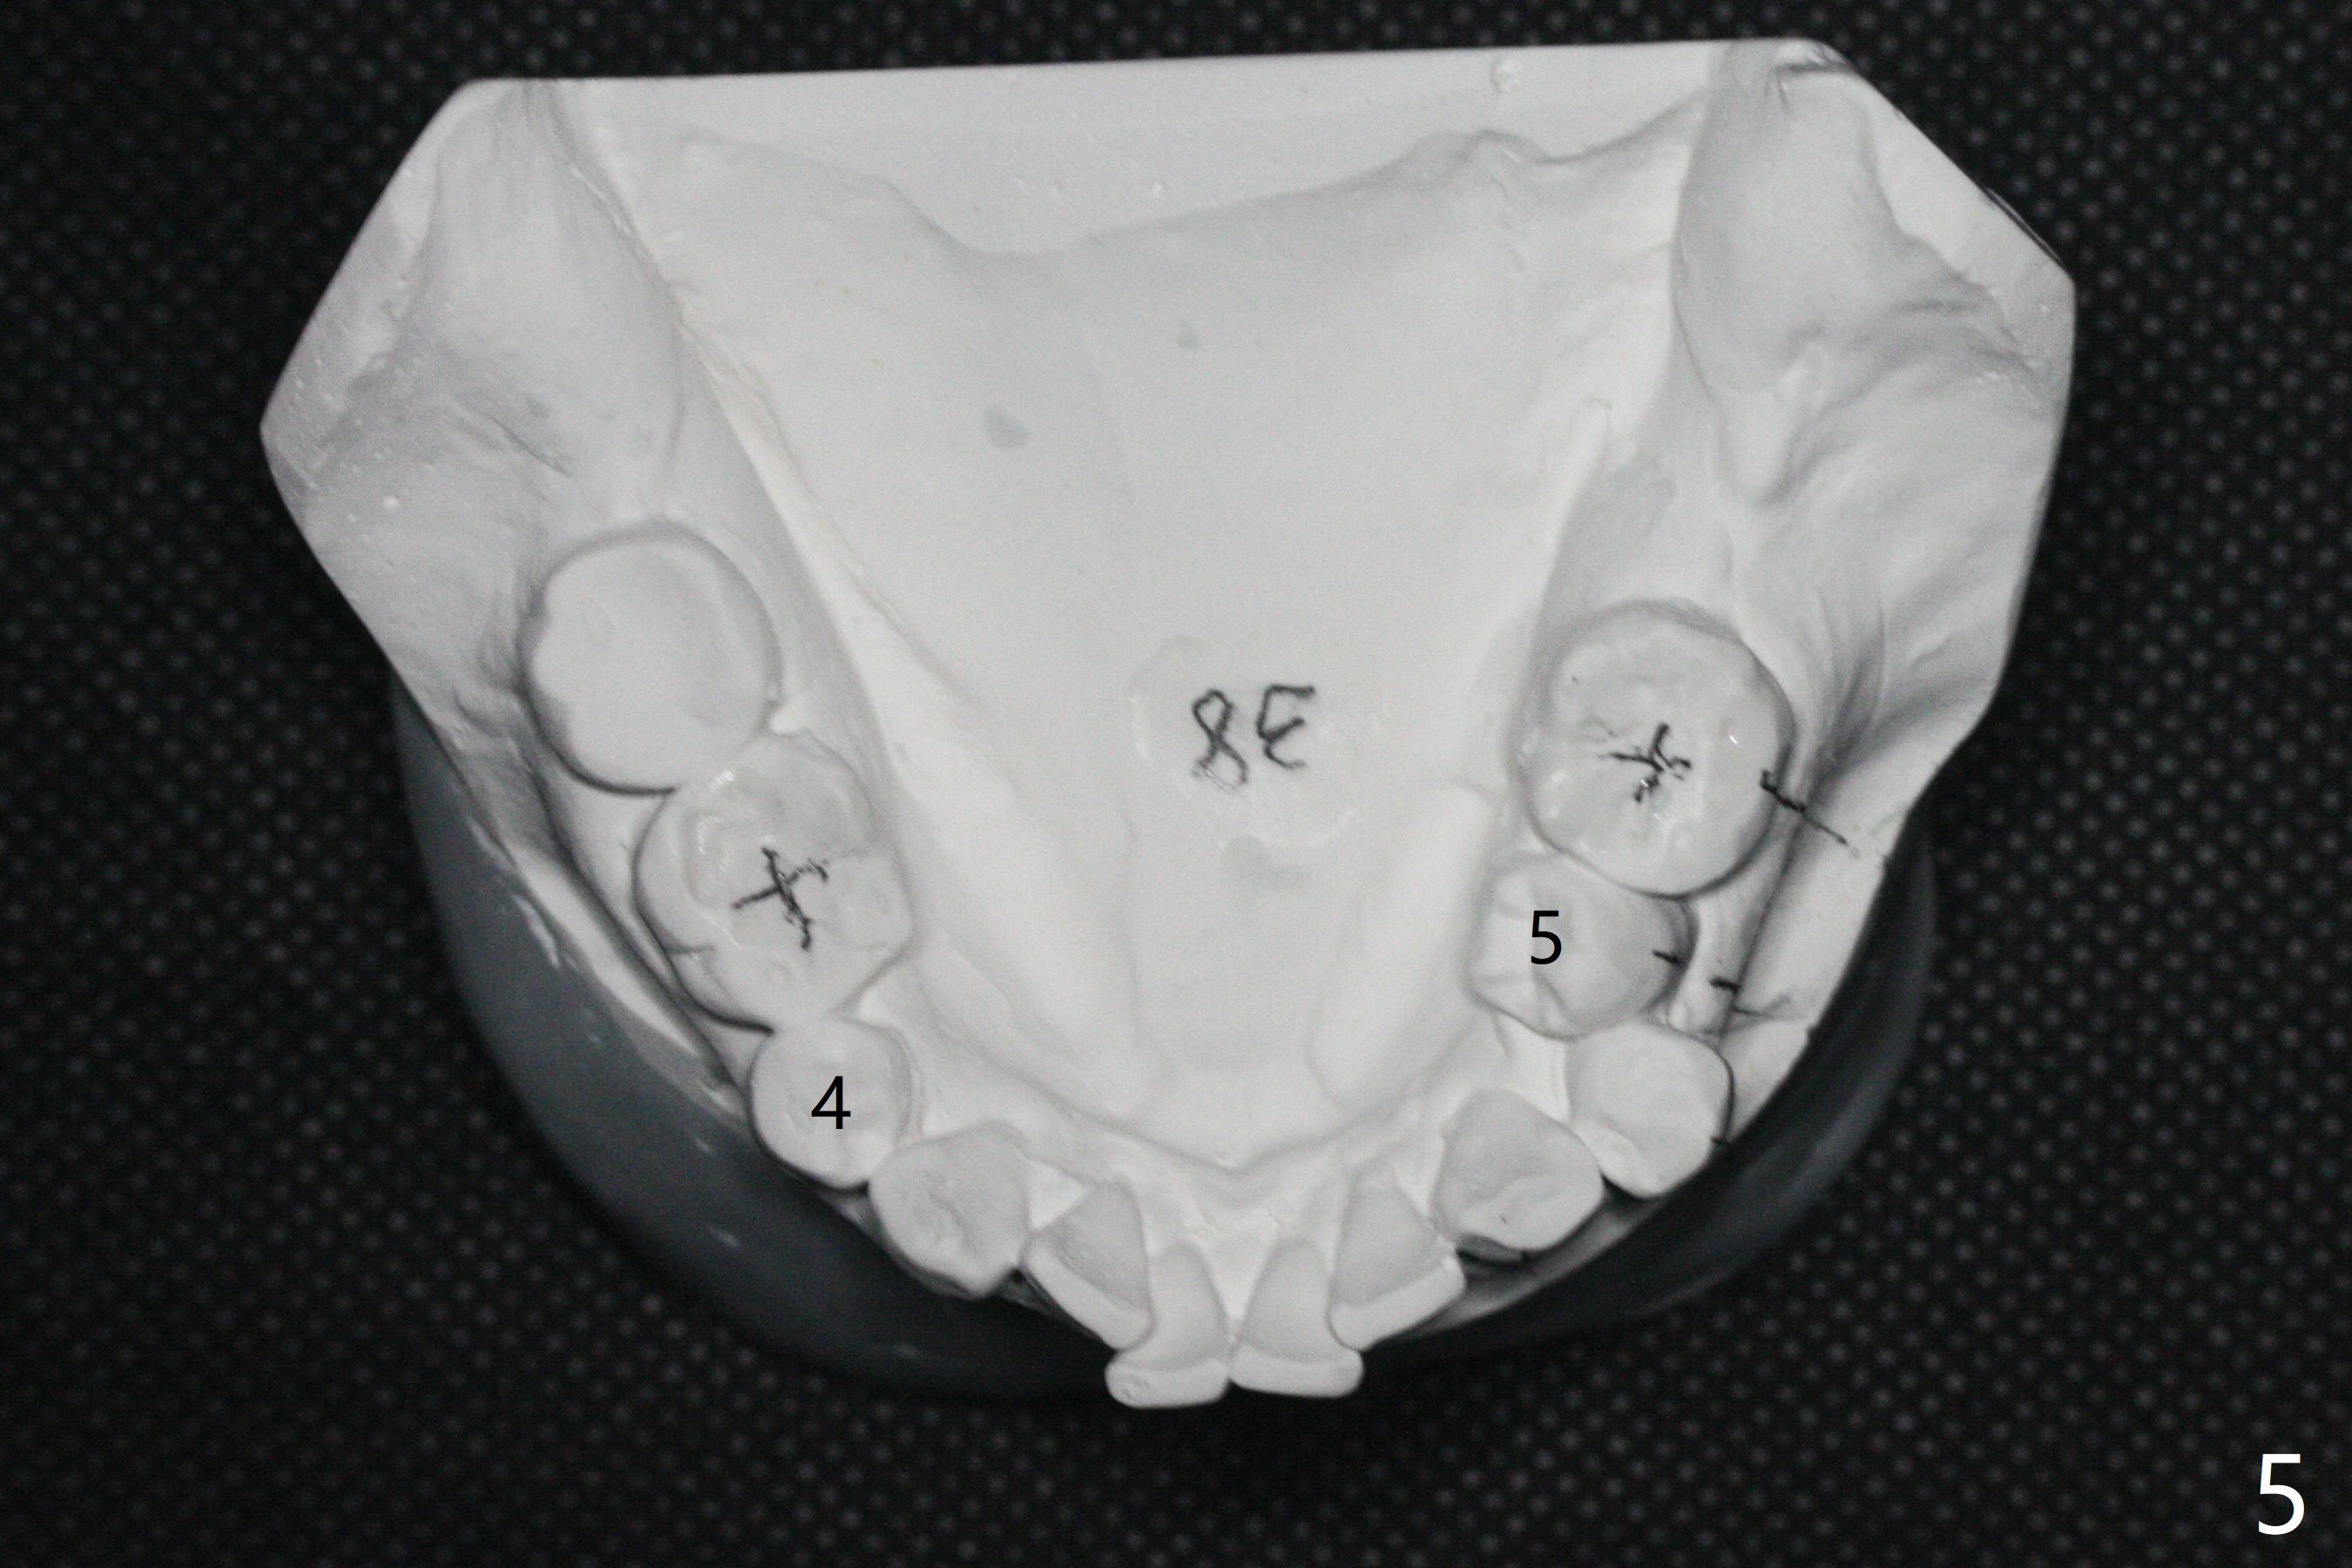

A 54-year-old man remains difficult in mastication in spite of implant placement at #14 and 31 (Fig. A, B, E, including screw loosening (poor trajectory at #14)). In addition to 2 more implants at #15 and 18 with guide, malocclusion seems to be necessary to be addressed (Fig.1-5). It appears that UR, LL4 should be extracted for orthodontic treatment (Fig.6-10). To reduce screw loosening, IS guide will be used to place IBS (5x9mm) and tissue-level (5x11mm) implants at #15 (PRF)and 18, respectively. If the one at #14 or 15 keeps loosening, splint #14 and 15 crowns. In fact the patient agrees with limited ortho (UR7 cross bite).